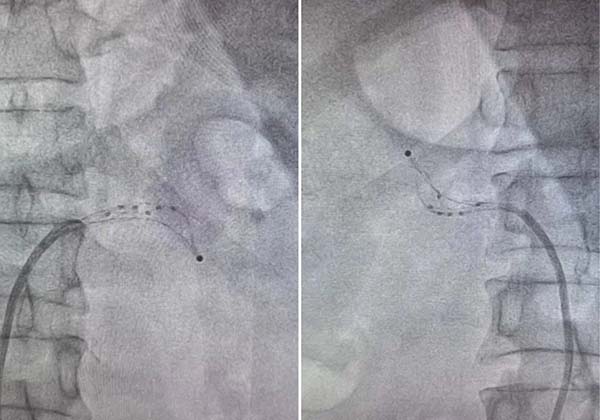

在造影明确双侧肾动脉解剖结构后,通过RDC导引导管将Netrod®星带®导管先后送达右肾动脉及左肾动脉。每到达一个靶点,先通过网篮贴壁检测确认电极与血管壁接触良好,再以45℃-60℃、120秒的标准参数释放射频能量。完成一处消融后,回收网篮、回撤导管2-5mm,再次展开贴靠,逐步由分支远端向主干开口“阶梯式”推进。整台手术历时约1小时,双侧肾动脉累计完成26个有效消融位点,术后即刻造影证实血管壁完整、血流达TIMI3级。术后患者恢复良好,顺利安返病房,术后次日血压便降至132/85mmHg,降压效果立竿见影。

导管在左右肾动脉贴壁影像